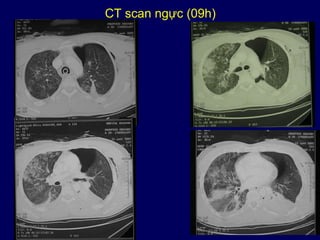

CT scan ngực (09h)

• Phế trường phải:

- hình như bông tuyết phế nang đậm lên

dưới màng phổi, không hệ thống

- đậm đặc ở đáy phổi

•Phế trường trái:

- tràn khí màng phổi trái phía thành trước

kèm tràn khí dưới da

•Trung thất bình thường